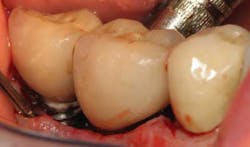

Fig. 3: After using Slimline ultrasonic, cement is removed.